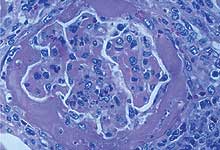

Porc atteint de SDN. La glomérulonéphrite fibrineuse (à gauche) et la vasculite nécrosante (à droite) sont les lésions histologiques caractéristiques de cette maladie.